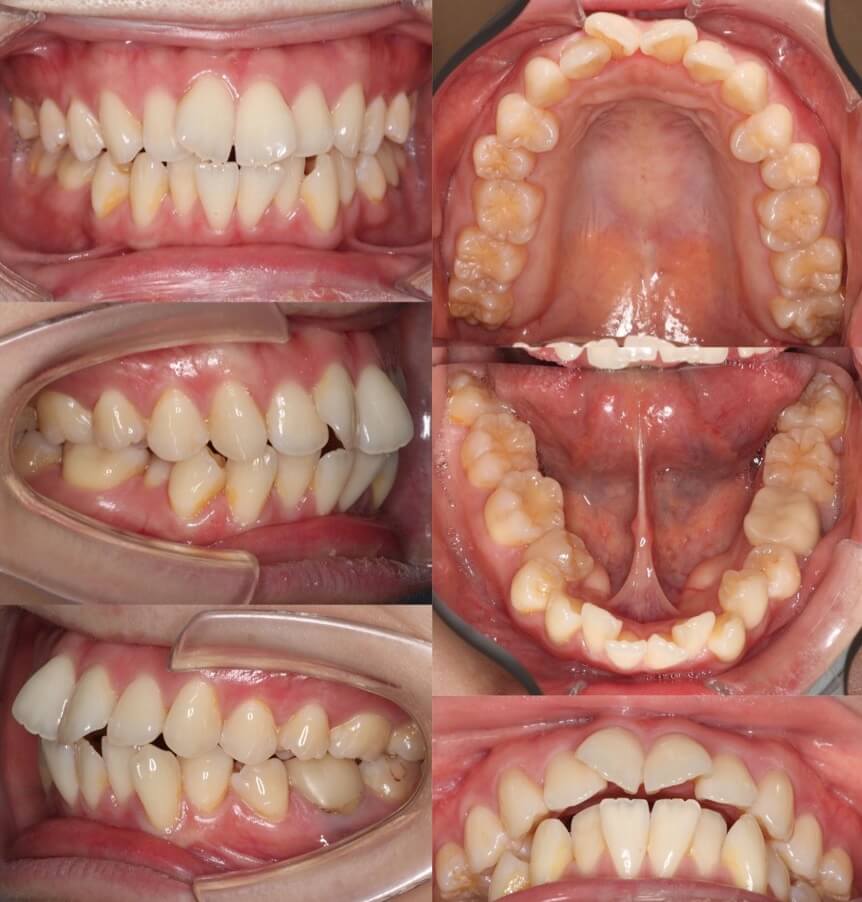

上顎前歯のトルクを加えた症例

前歯が前方に傾いている前突症例です。上下4本抜歯した空隙に、内傾させないよう上下の前歯を後方移動させました。上顎前歯のトルクコントロールは「クロージングループ」というモーメントを発生させるワイヤーを使用して行いました。

<症例概要>

主訴:前歯の前突

年齢・性別:20代女性

住まい:千葉県船橋市

症状:上下顎前歯唇側傾斜・叢生

治療方針:抜歯空隙閉鎖(中等度固定)

抜歯:上下第一小臼歯(計4本)

治療装置:唇側矯正装置

固定装置:ナンスホールディングアーチ

治療期間:1年9か月

リテーナー:上下プレートタイプ+フィックスタイプ

治療費用:990,000(税込)

代表的副作用:痛み・治療後の後戻り・歯根吸収・歯髄壊死・歯肉退縮